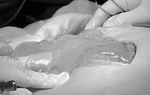

Khối u khổng lồ của bệnh nhân được bóc tách thành công.

Kết quả siêu âm của bệnh nhân cho thấy, có hình ảnh khối u kích thước lớn ở ổ bụng. Quá trình phẫu thuật, các bác sĩ đã bóc tách thành công khối u nặng 3kg.

Sau 2 tiếng thực hiện, các bác sĩ đã bóc tách thành công khối u buồng trứng nặng 3kg. Sau phẫu thuật, sức khỏe bệnh nhân đã ổn định, hiện tiếp tục được theo dõi tại BV.